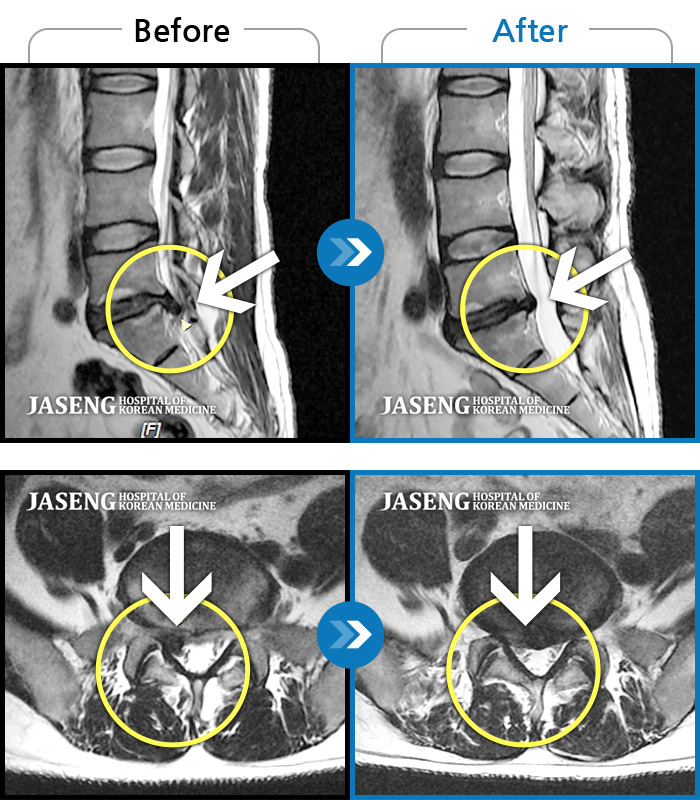

MRI 치료사례

일어서질 못할 정도의 다리 통증